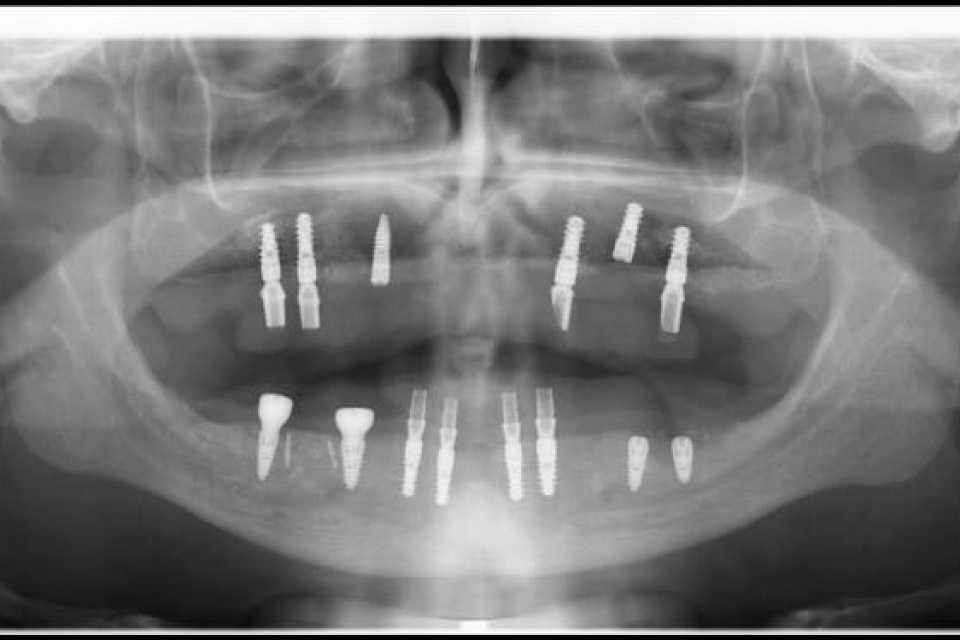

Pe parcursul unui an s-au efectuat adiții osoase la nivelul maxilarului (sinus lifting) și al mandibulei (tehnica Khoury, adiție laterală și verticală a zonei molarilor și premolarilor) cu ajutorul cărora am reușit inserarea a 6 implanturi Straumann la nivel maxilar și 8 implanturi dentare mandibular (4 Straumann, 4 MegaGen Anyridge).